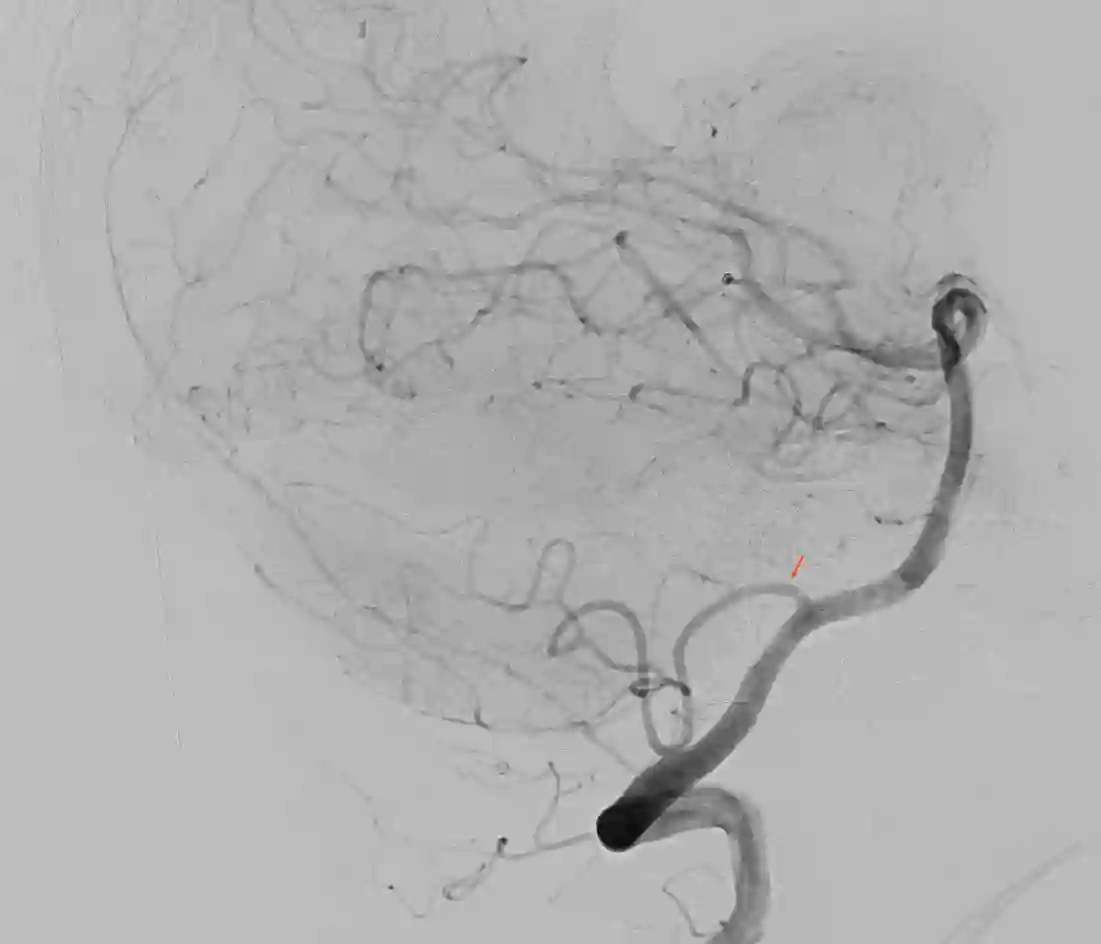

Die PICA entspringt in der Regel direkt aus der Arteria vertebralis. Üblicherweise entspringt die PICA hierbei ca. 10 mm distal zu jenem Punkt, wo die Arteria vertebralis intradural wird und etwa 15 mm proximal zur vertebrobasilären Verbindung[^1]. In etwa 5-8 % der Fälle hat die PICA einen extraduralen Ursprung[^1]. Eine weitere anatomische Variante ist die AICA-PICA, hierbei entspringt die PICA aus der Arteria basilaris an gleicher Stelle wie die AICA. Die PICA zeigt angiographisch eine craniale- und caudale Schleife sowie den Choroidal Point. Die PICA kann in fünf verschiedene Segmente eingeteilt werden[^4]:

Bildgebung

Aneurysmen

Aneurysmen an der PICA stellen 0,49 bis 3 % aller cerebralen Aneurysmen dar [^1] [^6].